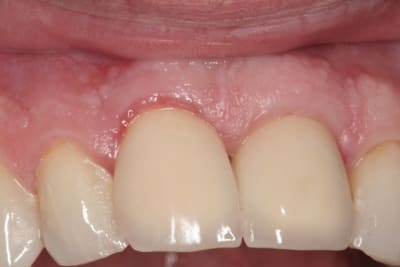

le hasard fait parfois bien les choses...patient revu ce matin pour une "bricole" sur une restauration postérieure...

il est intéressant de voir la maturation des tissus mous...et en plus VS des différences au niveau de l'hygiène, pas mal secteur 2 mais perfectible secteur 1...

ici on est à 3 mois post pose prothèses d'usage...la photo, prise un peu décalée, donne l'impression d'une différence de hauteur des collets, mais il n'en est rien (ou alors très peu...)

quand même content du résultat...;-) même si j'ai (lourdement)insisté pour que l'hygiène soit un peu mieux suivie...

Img 3109 susrjd - Eugenol